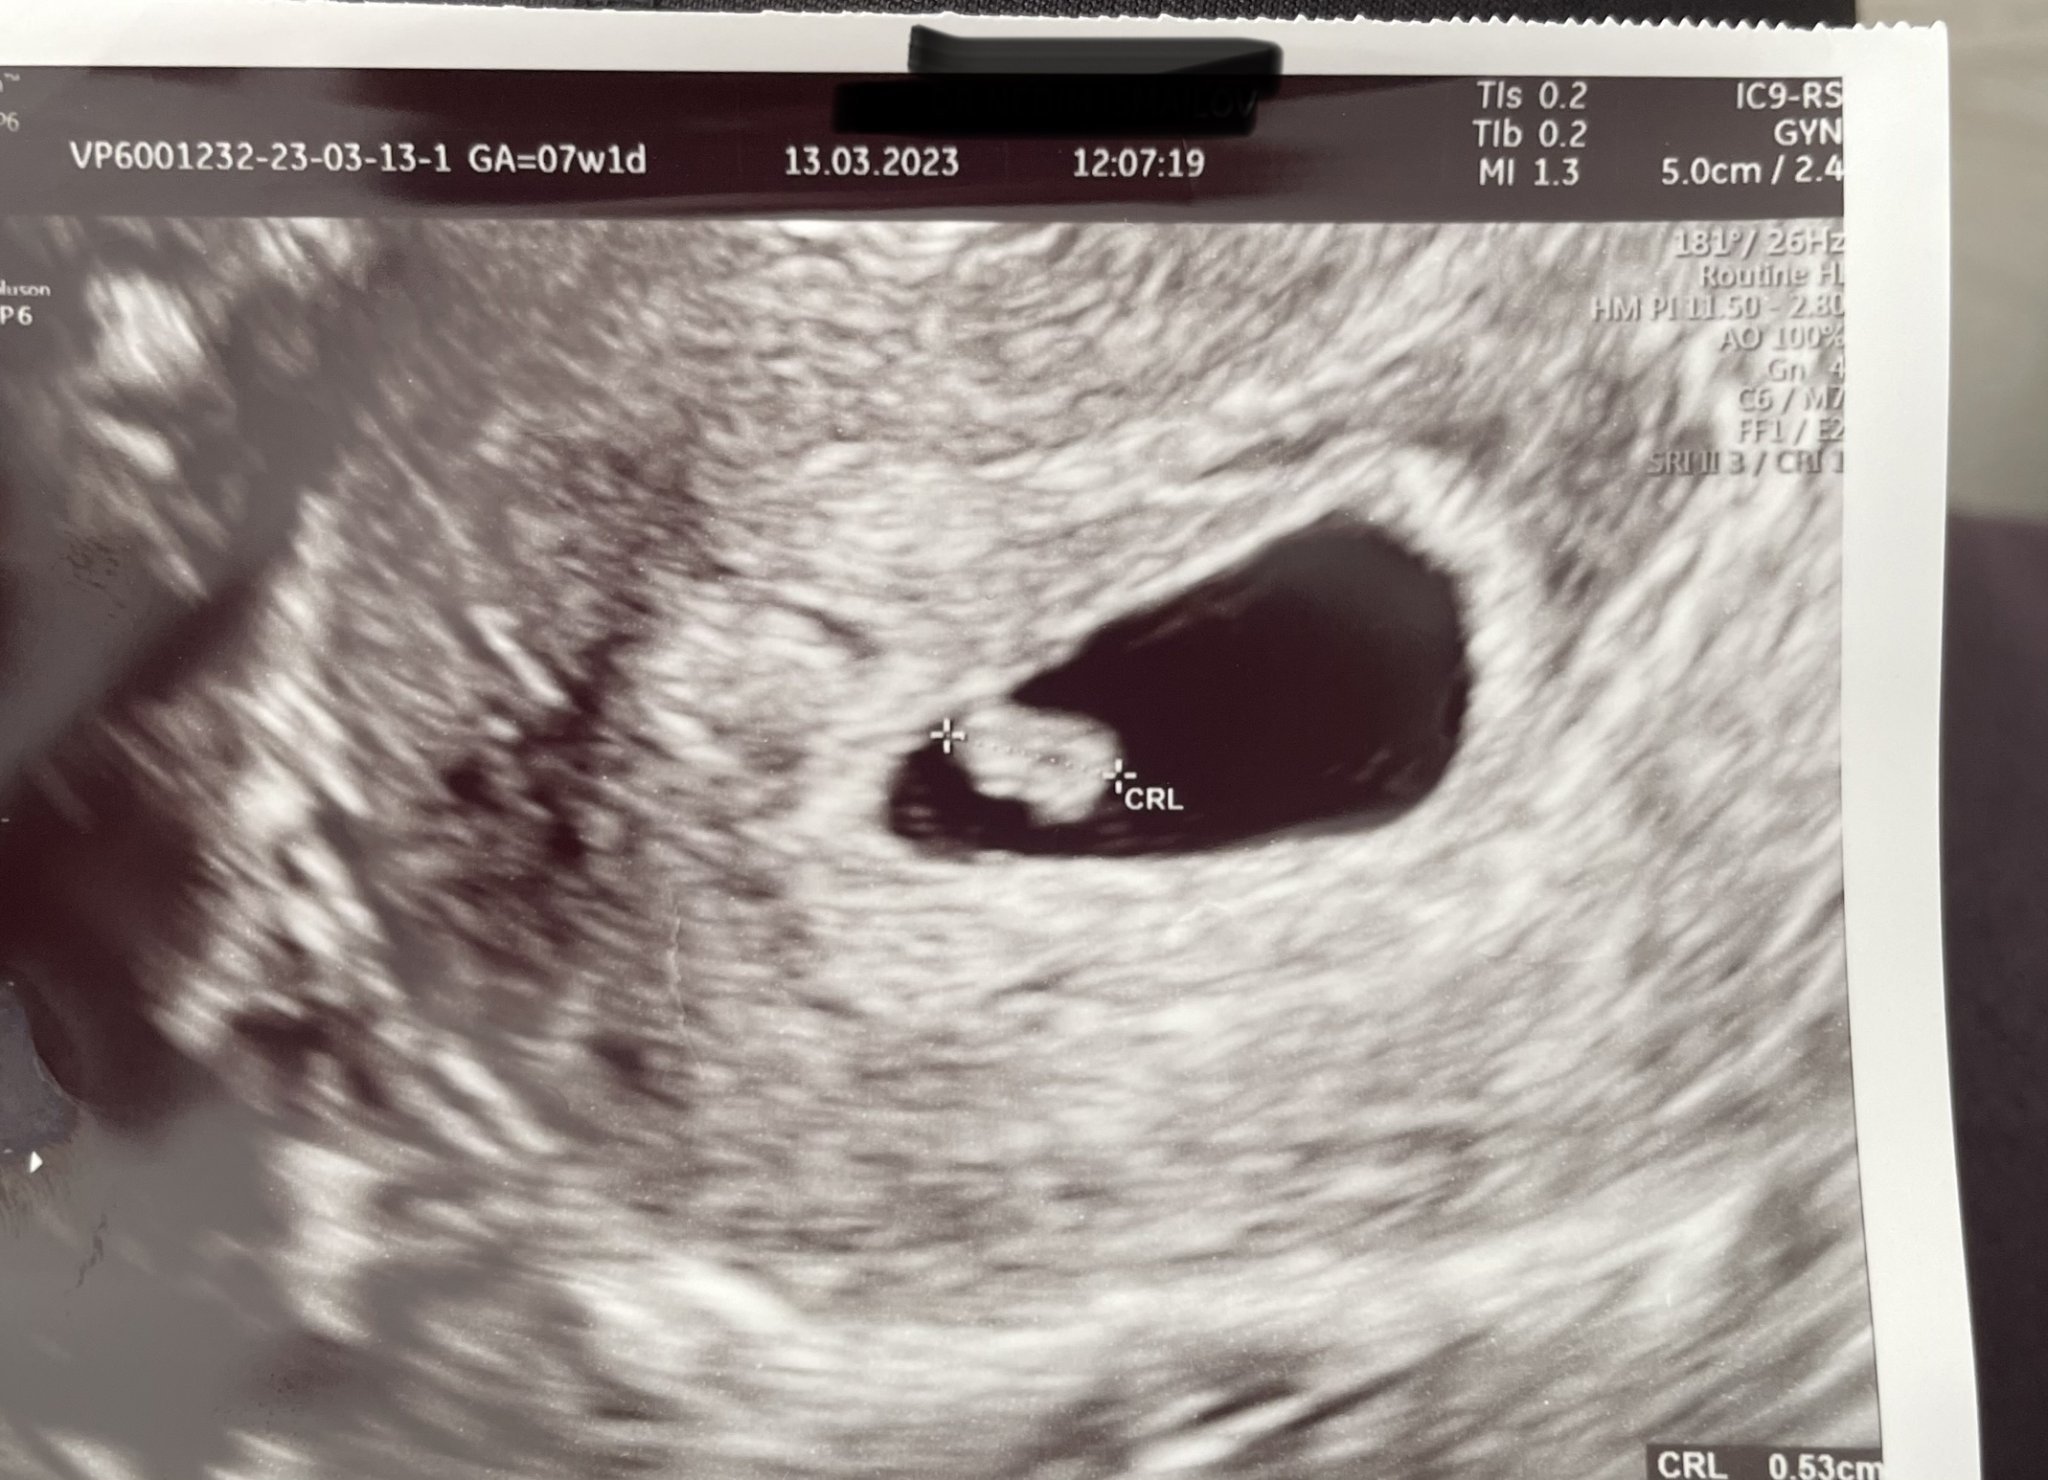

Записването на преглед зависи от индивидуалните обстоятелства, но обикновено лекарите препоръчват да изчакате поне 10 дни след закъснението, за да потвърдите бременността. В началото може да е твърде рано за откриване на пулсации, които обикновено се появяват около 8-та седмица. Ако забележите кървене или други симптоми, важно е да се консултирате с вашия лекар.